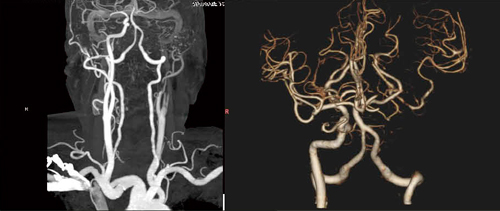

図2 症例2のCTA画像(Definition Flash)

左内頸動脈閉塞。中大脳動脈の末梢は描出されている。

図4 症例2:4D CTAによる脳血流動態評価

側副血行路を介した逆行性の血流が認められる(←)。